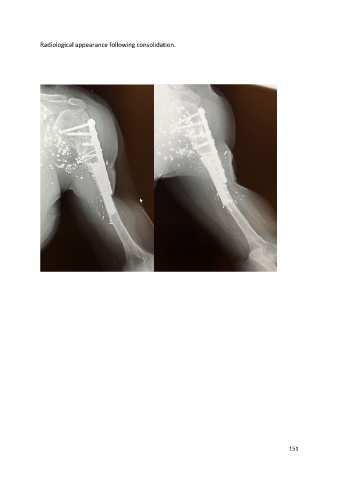

Radiological appearance following consolidation.